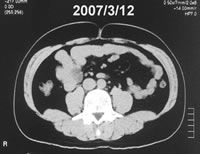

| 図5 治療前後の推移(腹部CT) 千葉健生病院放射線科 佐藤元氏計測 |

||||||||||||||

![]() |

⇒ | ![]() |

||||||||||||

◆上のへこみがおへそ。黒く見える部分が脂肪。7カ月で脂肪はほぼ半減 |